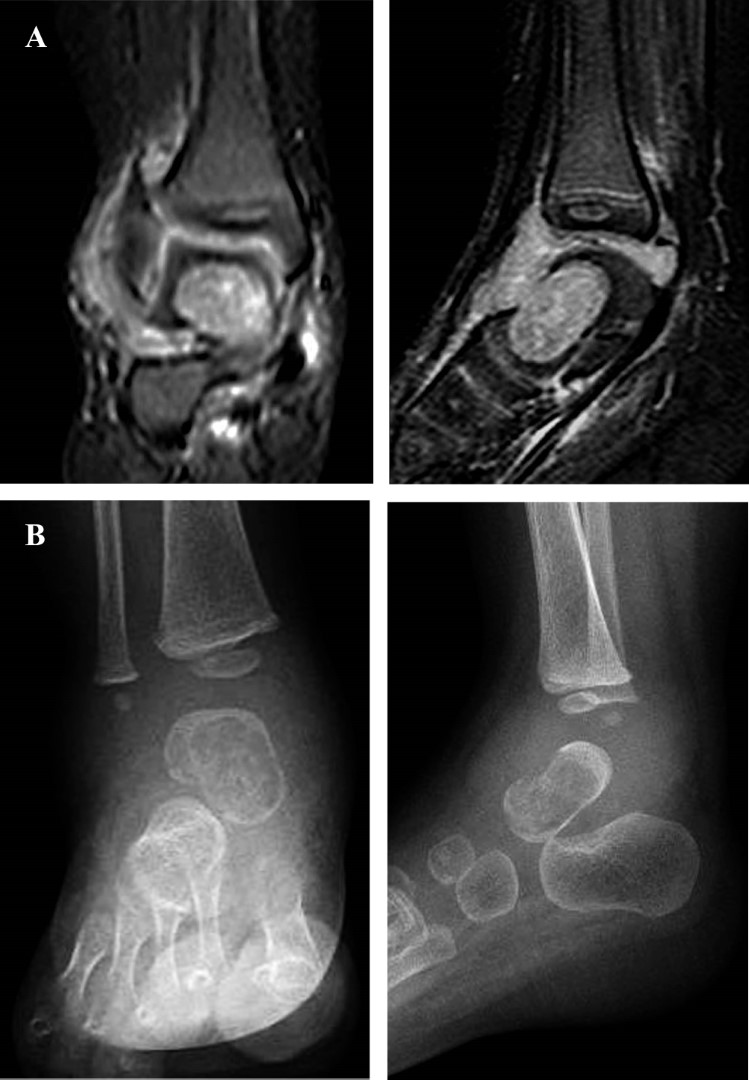

Figura 2

Figura 3